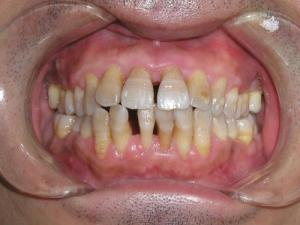

牙床萎缩主要是龈缘部分存在异物又长期得不到清理,细菌滋生刺激长期存在所致;

另外随着年龄的增长也会或多或少发生萎缩。

再就是牙科手术不当留下的后遗症。

保持清洁是延缓牙龈萎缩的最有效的方法,定期洗牙亦显得尤为重要。

炎症性的牙龈萎缩,主要表现为牙龈红肿胀痛,刷牙时常见出血。

而老年牙龈萎缩常使裸露了的牙极对冷热的温度变化及酸性食物等异常敏感,妨碍进食,降低生活质量,尢应注意防治。